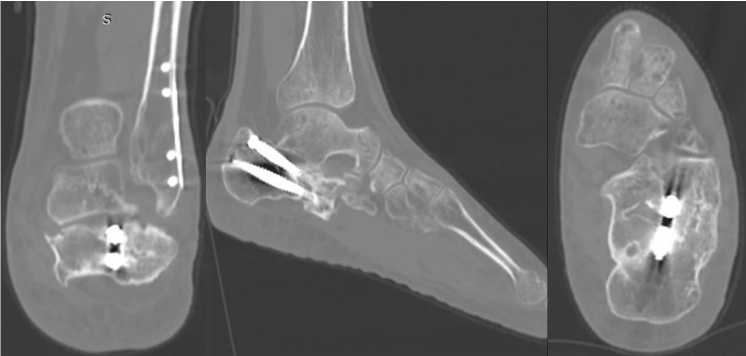

Рис. 5. Рентгенограммы левой стопы в прямой и боковой проекциях под нагрузкой весом тела

Для уточнения хода линий перелома, взаиморасположения и степени консолидации фрагментов пяточной кости пациенту выполнена МСКТ левой пяточной кости, в ходе которой подтвержден исходный суставно-депрессионный характер перелома, выраженный пяточно-малоберцовый конфликт, а также уточнены форма и взаиморасположение консолидированных фрагментов пяточной кости и металлоконструкций (рис. 6).

Рис. 6. МСКТ левой стопы в коронарной, саггитальной и аксиальной плоскостях [16]